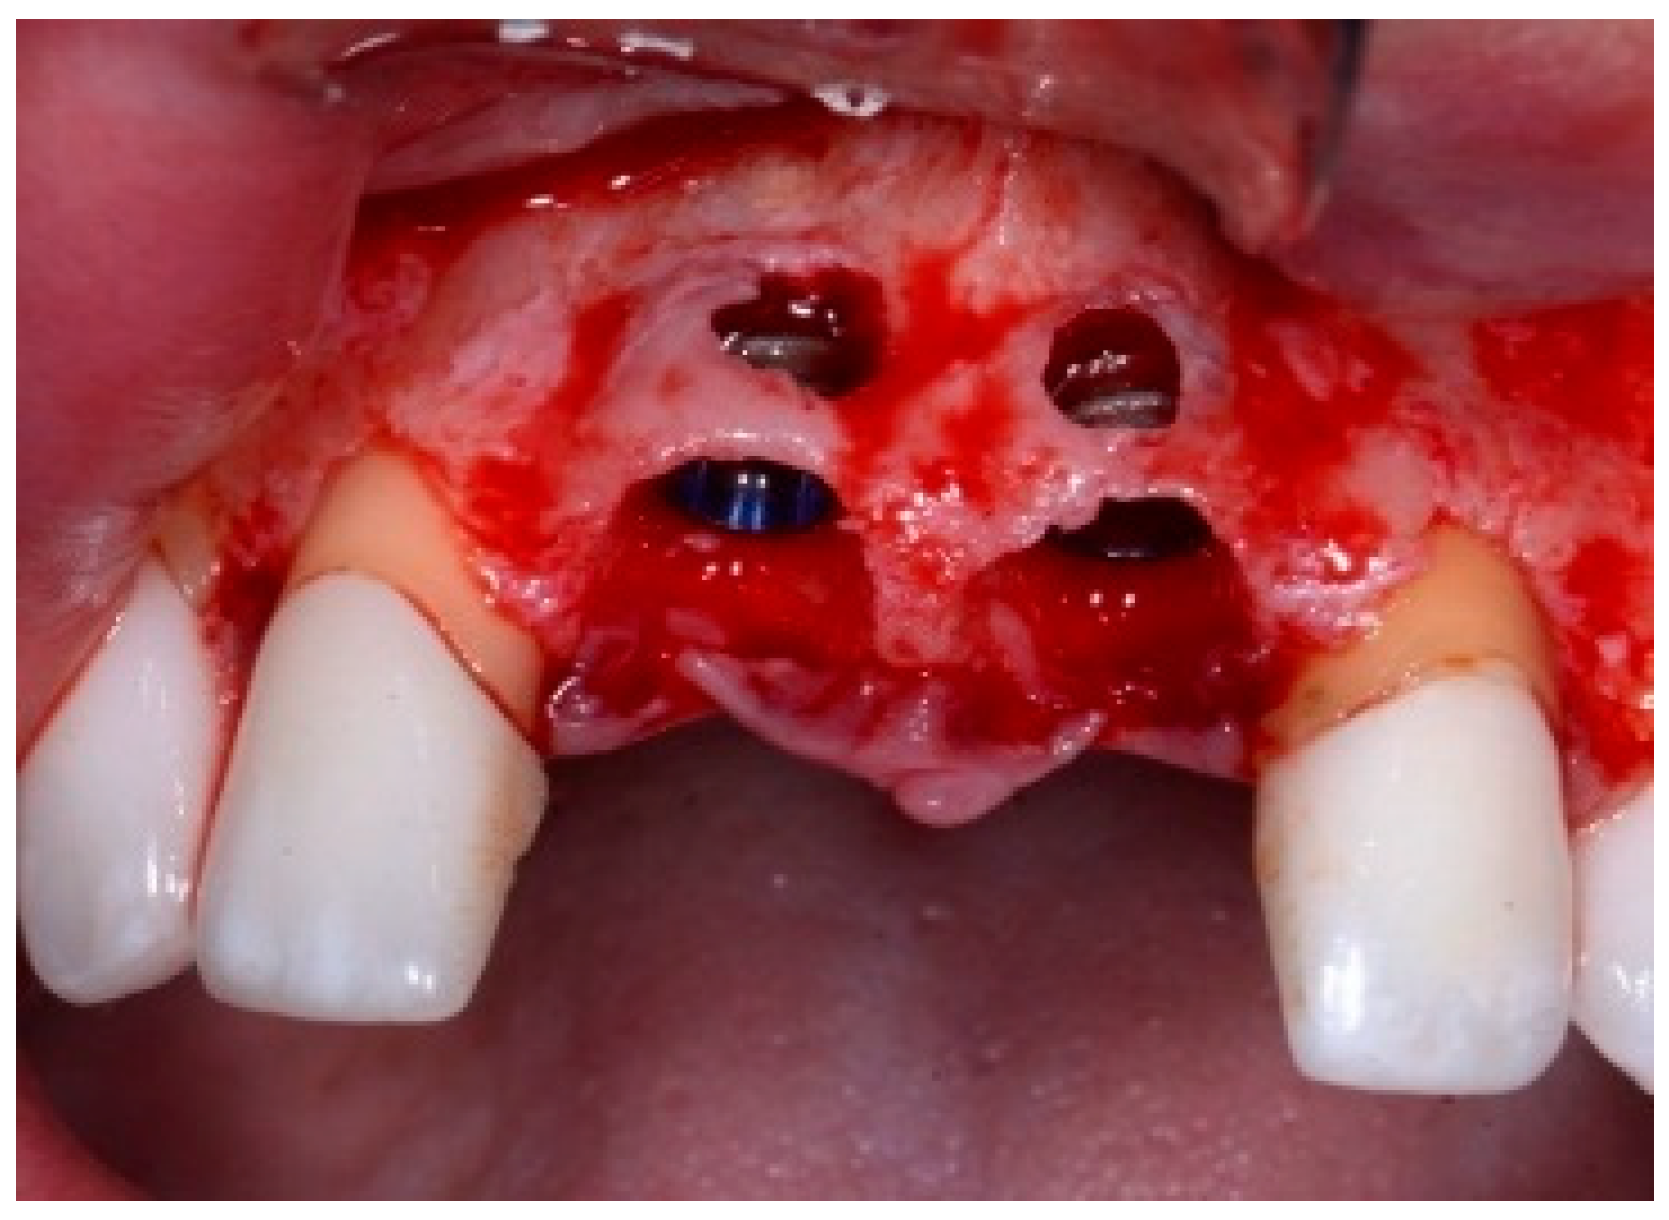

One hour before the surgical procedure, the patient received a prophylactic dose of 1 g of amoxicillin. Following local anesthesia, surgical access was obtained by raising a full-thickness aesthetic flap extending to the distal line angles of the lateral incisors. The full-thickness flap was extended 3–5 mm beyond the apical margin of the defect. The two central incisor roots were extracted, and the sockets were curetted with surgical curettes to remove all the granulation tissue (Figure 2). The sockets were assessed for the presence of a dehiscence and or fenestration. Two implants (Adin Dental Implants, Englewood, NJ, 07632, USA) were placed according to the manufacturer’s instructions (Figure 3).

Figure 3.

Clinical view of the placement of two maxillary anterior implants.